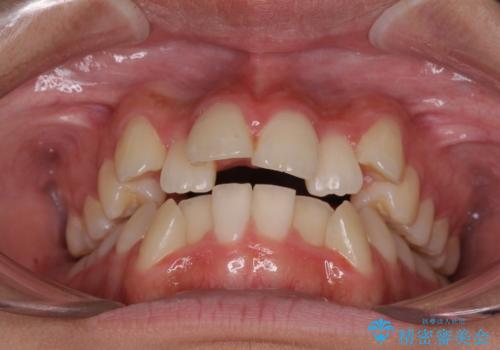

- 歯列全体の叢生を気にして来院された患者様です。

検査を行った結果、上顎骨の横幅が相対的に狭いことが分かり、叢生が強いことから、急速拡大装置にて上顎骨を側方に拡大することで、叢生の解消と奥歯の咬み合わせ改善を図ることとしました。

一般的には上下左右の第一小臼歯4本を抜歯する必要がありますが、拡大量によっては非抜歯矯正の適用となる可能性があるため、まずは非抜歯矯正で治療を開始し、抜歯が必要と判断された時点で速やかに4本抜歯を行うこととしました。